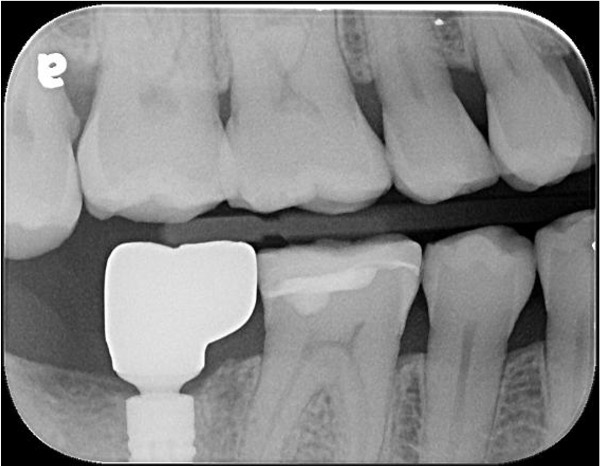

治療前,二次蛀牙,咬頭受損

蛀牙未到牙髓

冠塊體體製備

術前、術後比較